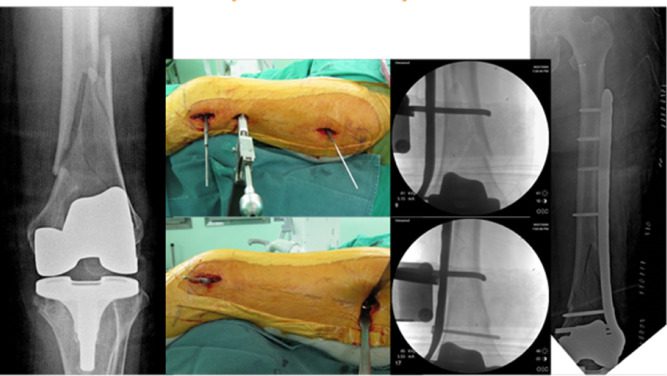

جراحی شکستگی و دررفتگی‌های ستون فقرات برای بازگرداندن پایداری به مهره‌ها و جلوگیری از آسیب نخاع انجام می‌شود. این عمل معمولاً شامل تثبیت ستون فقرات با پیچ و پلاک یا انجام فیوژن مهره‌هاست تا حرکت غیرطبیعی متوقف شود.

شکستگی ناشی از پوکی استخوان در مهره‌ها می‌تواند باعث درد شدید و محدودیت حرکتی شود. در موارد شدید، جراحی مانند کیفوپلاستی یا ورتبروپلاستی برای ترمیم مهره و کاهش درد انجام می‌شود و معمولاً روش‌های کم‌تهاجمی به کار می‌رود.